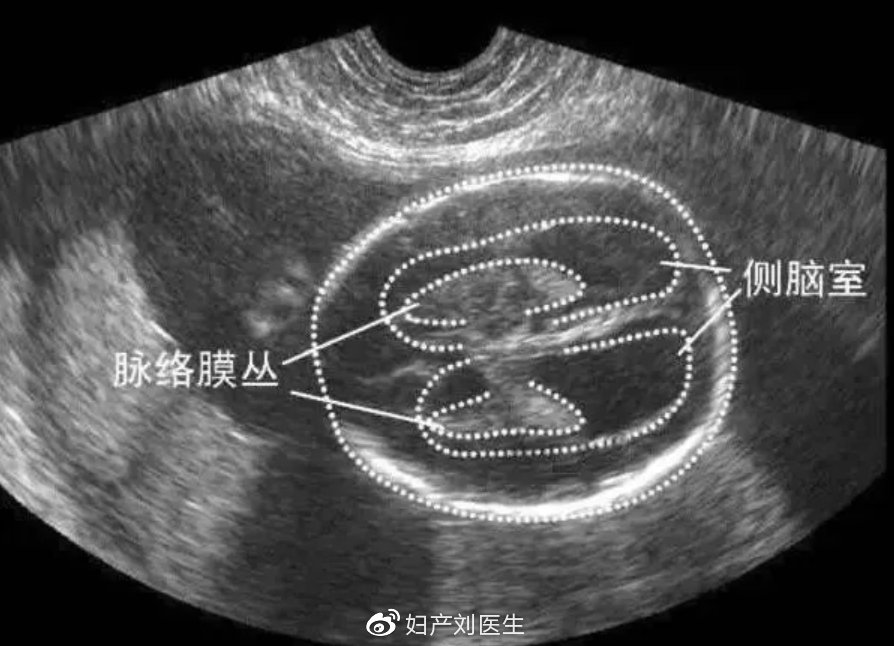

侧脑室增宽(Lateral ventricle broadening),是孕中晚期超声测量胎儿侧脑室体部宽度的超声征象。侧脑室宽度测定是产前超声检查判断胎儿神经系统疾病及病变程度的标准方法。正常侧脑室体部宽度≤10mm,平均7mm,侧脑室宽度大于10mm称为侧脑室增宽。对于合并其他部位结构异常或染色体异常患儿来说,不建议继续妊娠。

脑室宽度≥15mm,也可称为脑积水,是脑脊液过多积聚于脑室系统中,侧脑室系统扩张,压力升高,超声检查时表现为脑室增宽。一般侧脑室三角区增宽达1.5厘米认为脑室扩大,且越宽程度越重。如果三角区宽1.2~1.4厘米,脉络丛占满脑室内大于50%时,一般认为正常。如脉络丛缩小并呈悬挂状态时,则认为有脑积水存在。